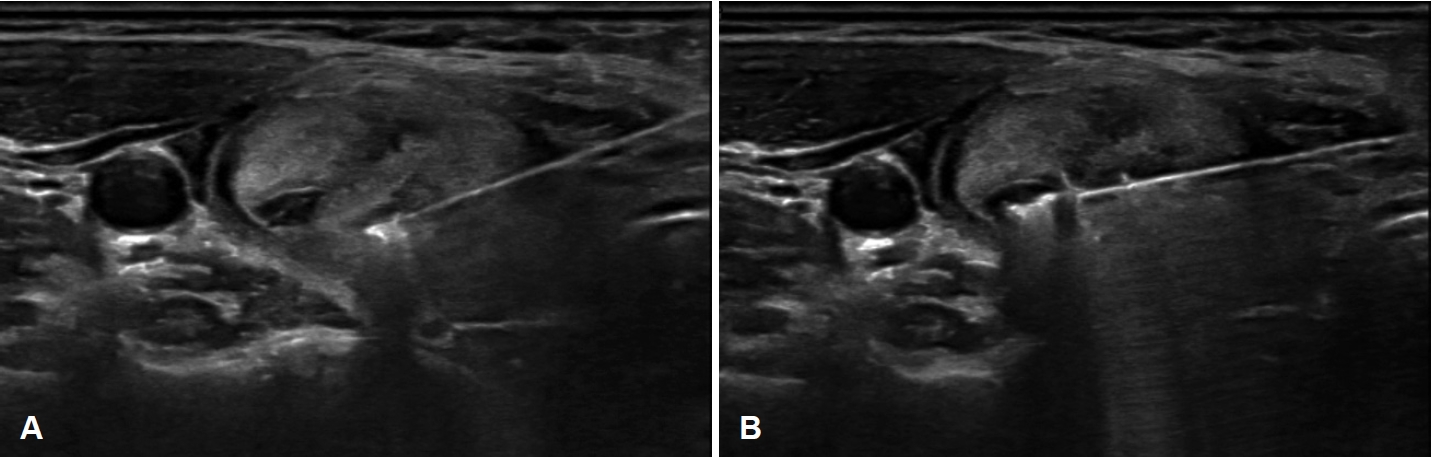

NotesAuthor Contribution Conceptualization: Dongbin Ahn. Data curation: Hyowon Ahn. Investigation: Dongbin Ahn. Methodology: Soobi Ham. Project administration: Soobi Ham. Resources: Dongbin Ahn, Soobi Ham. Software: Soobi Ham. Validation: Hyowon Ahn. Visualization: Dongbin Ahn. Writing—original draft: Dongbin Ahn, Hyowon Ahn. Writing—review & editing: Dongbin Ahn. Fig. 1.Positional setting for radiofrequency ablation. For righthanded operators performing procedures on right thyroid nodules, the ultrasound machine and equipment are placed above the patient’s head, with the surgeon standing on the patient’s right side. Fig. 2.Schematic figure of trans-isthmic approach and moving shot technique in radiofrequency ablation. An electrode needle is inserted through the isthmus, and ablation begins from the deepest and most medial compartment of the tumor. Utilizing the moving shot technique, the tumor is continuously ablated in a unit-byunit manner. T, trachea; E, esophagus; I, internal jugular vein; C, carotid artery; V, vagus nerve. Fig. 3.Ultrasound images of the moving shot technique. A: To minimize artifacts caused by the electrode needle and ablation, the process begins with the deepest and most medial compartment of the tumor. The electrode needle is then moved backward to ablate the remaining compartments along its insertion path. B: To treat the more superficial compartments, the insertion axis of the electrode needle is adjusted, and ablation is performed in the same manner. Fig. 4.Anterolateral hydrodissection. A: A mass (M) is identified in the right thyroid gland. B: Anterolateral hydrodissection is performed by instilling a cold 5% dextrose solution (asterisk) to separate the right thyroid gland from the carotid artery (C). Arrows indicate 25-gauge needle inserted for injection. Fig. 5.Posteromedial hydrodissection. A: A mass (M) is identified in the right thyroid gland. B: Posteromedial hydrodissection is performed by instilling a cold 5% dextrose solution (asterisk) to separate the mass from the danger zone. Fig. 6.Longitudinal and oblique approaches for radiofrequency ablation. A caudocranial insertion of the electrode (arrows) parallel to the long axis of the thyroid gland (A), or an oblique insertion (B), can also be used safely as long as the entire length of the electrode is monitored on real-time ultrasound. The trachea is not depicted in the current images as they are obtained from longitudinal (A) and oblique views (B). C, carotid artery. REFERENCES1. Durante C, Grani G, Lamartina L, Filetti S, Mandel SJ, Cooper DS. The diagnosis and management of thyroid nodules: a review. JAMA 2018;319(9):914-24.